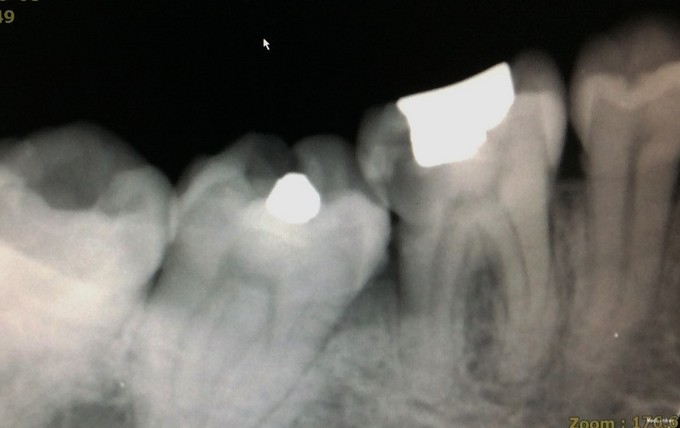

诊断:46牙慢性牙髓炎 治疗:46牙根管治疗+充填修复+桩冠修复 治疗经过: 首诊:去除原树脂充填物,去净龋坏,开髓,止血,封“三聚甲醛”。 首次复诊:46牙上橡皮障,揭全随室顶,显微镜下探查根管口,3根管牙,清理髓腔,#08,#10,#15不锈钢K锉疏通根管,根测仪测量根管长度,近颊根19mm,近舌根18.5mm,远中根20mm;EDTA润滑剂作用下,机用镍钛器械Protaper清扩至#2506锥度,远中根#3004,K锉疏通至#40;示尖到位;超声荡洗,次氯酸钠冲洗,干燥,根管内封氢氧化钙,髓腔置干棉球,CAVITON暂封。 二次复诊:46牙上橡皮障,去暂封,荡洗根管,次氯酸钠冲洗,干燥根管,AH糊剂加大椎度牙胶充填根尖段根管,热牙胶封闭上段根管;远中根预备纤维桩道,粘接纤维桩,行牙体树脂粘接修复。建议观察1周,若无明显不适,至修复可行冠修复。建议牙周科会诊46牙。

讨论: 1、下颌第一磨牙3根管最常见,上图清晰展示了开髓后根管口的分布。寻找根管口应注意寻找是否有远舌根,因为远舌根通常位置靠近远中边缘,若随室顶没揭全,易遗留。 2、根管预备应注意根尖孔大小。下颌磨牙通常远中根根尖孔较近中根根尖孔直径更大,行预备时应注意用K锉试探根尖孔预备是否恰当。 3、AH糊剂调拌的状态可能会影响根充的质量。本病例中,近中根、远中根均有不均匀高密度影,为相对较稠的AH糊剂。根充时应注意AH糊剂是否已固化,且应在根管中上下提拉主牙胶尖数次以使糊剂充分到达根尖处,且均匀分布于根管内。 4、若远中根根管粗大,可充填副尖以更好地封闭根尖段。 5、从该病例中可发现,远中根根尖孔开口应位于远中,不在根尖。因根尖孔的解剖位置差异大,根管治疗应充分利用根测仪测量准确的长度,不能仅凭X线片来判断。